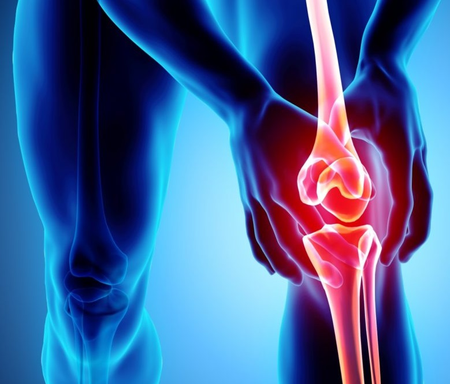

आजकाल सांध्यातील वेदना, कडकपणा व सूज ही अतिशय सामान्य समस्या झाली आहे. पूर्वी ही तक्रार प्रामुख्याने वयस्कर लोकांमध्ये दिसायची, पण आता तरुण वयातही लोक या त्रासाने पीडित आहेत. आयुर्वेदात अस्थिवात (आर्थ्रायटिस) ही एक गंभीर व्याधी मानली जाते. याचे अनेक प्रकार आहेत, त्यापैकी ऑस्टिओआर्थ्रायटिस (वय वाढल्यावर होणारा) आणि रुमॅटॉइड आर्थ्रायटिस (स्व-प्रतिकारशक्तीशी निगडित आजार) हे सर्वाधिक सामान्य आहेत.

आयुर्वेदनुसार शरीराची पचनक्रिया दुर्बल झाली की, अपूर्ण पचलेले अन्न शरीरात आम (विषारी द्रव्य) म्हणून साठू लागते. हे आम वात दोषाबरोबर एकत्र होऊन सांध्यामध्ये जमा झाले की त्याला आमवात (रुमॅटॉइड आर्थ्रायटिस) म्हणतात. ही अवस्था फार वेदनादायक असून संपूर्ण शरीरात जकडणूक, सांध्यांची सूज आणि तीव्र वेदना निर्माण करते. तर, जर वात दोष रक्तदोषाबरोबर एकत्र झाला, तर तो सांध्यात अडथळा व सूज निर्माण करतो आणि त्याला वातरक्त (गाऊट) म्हणतात.

आयुर्वेदात गठियाचा उपचार फक्त लक्षणं दडपण्यापुरता मर्यादित नसून, तो रोगाच्या मूळ कारणावर कार्य करतो. यात आहार-विहार (खानपान व जीवनशैली), पंचकर्म चिकित्सा, औषधीं आणि योग-प्राणायाम यांच्या साहाय्याने संतुलन प्रस्थापित केले जाते. प्रथम रुग्णाची पचनसंस्था सुधारण्यासाठी दीपन-पाचन औषधीं वापरतात (उदा. त्रिकटु, हिंग्वाष्टक चूर्ण). त्यानंतर शरीरात साठलेले आम बाहेर काढण्यासाठी स्नेहन, स्वेदन आणि मग वमन किंवा विरेचन यांसारख्या पंचकर्म पद्धतींचा अवलंब होतो.

गठियाच्या उपचारात वापरली जाणारी मुख्य आयुर्वेदिक औषधे म्हणजे महारास्नादि क्वाथ, योगराज गुग्गुळु, सिंहनाद गुग्गुळु, अश्वगंधा चूर्ण, दशमूल क्वाथ, आणि शुद्ध शिलाजीत. ही औषधे वात दोष शमवतात, सूज कमी करतात आणि सांध्यांची कार्यक्षमता वाढवतात. त्याचबरोबर रुग्णाने जड, तुपकट, आंबट व जड पचणारे अन्न टाळावे, कारण हे वात आणि आम वाढवतात. गरम पाणी, हलकं सुपाच्य अन्न आणि नियमित व्यायाम करण्याचा सल्ला दिला जातो. योग व प्राणायामही गठियाच्या व्यवस्थापनात उपयुक्त ठरतात. विशेषतः वज्रासन, त्रिकोणासन, भुजंगासन यांसारखी आसने सांध्यांची लवचिकता टिकवून ठेवतात आणि वेदना कमी करतात. प्राणायामात अनुलोम-विलोम आणि भस्त्रिका वात संतुलित करण्यात मदत करतात. याशिवाय, एकाच ठिकाणी खूप वेळ बसून राहणे टाळावे.